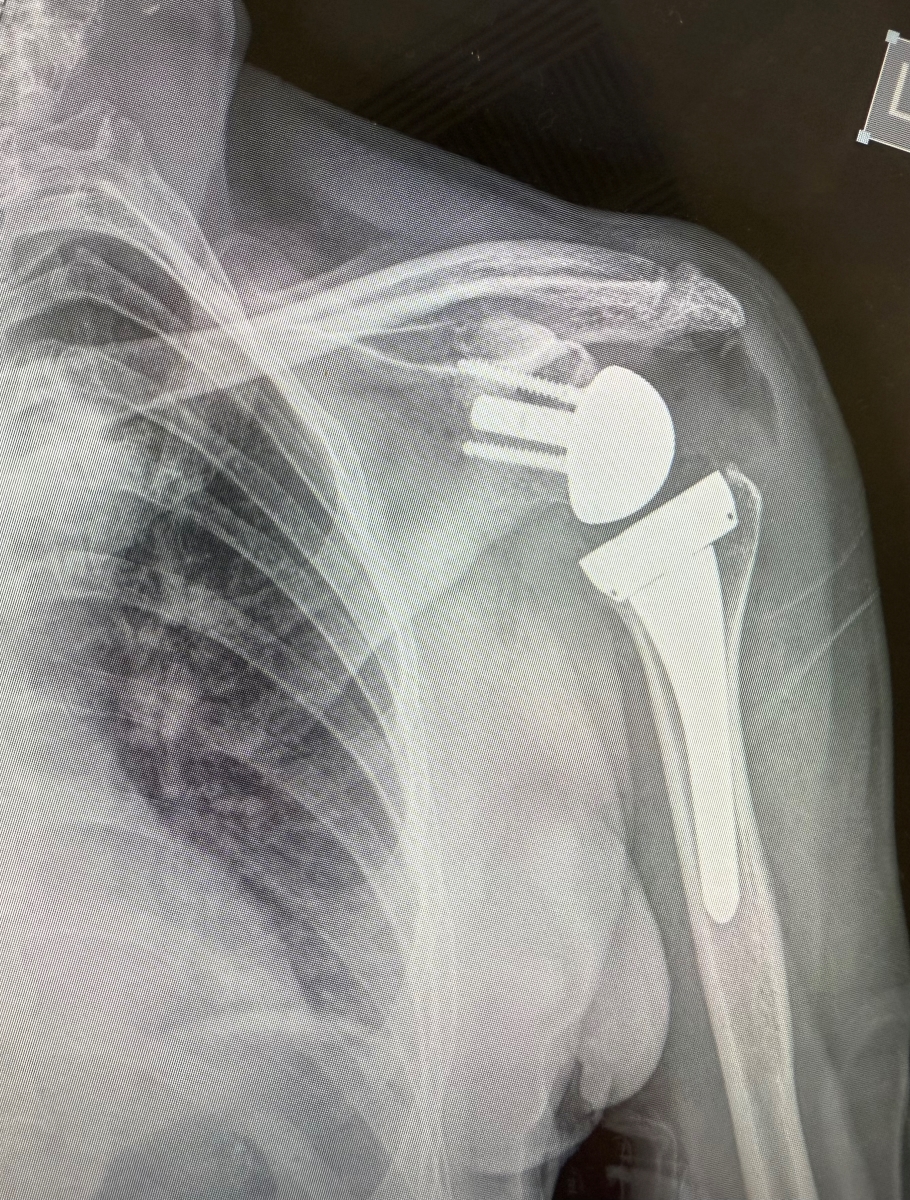

Η ανάστροφη αρθροπλαστική ώμου είναι πλέον η πιο συχνή μέθοδος αντικατάστασης της άρθρωσης του ώμου, η οποία διαφέρει από την κλασική αρθροπλαστική ως προς τον σχεδιασμό, καθώς έχει “ανάποδο” σχήμα, γι’ αυτό και ονομάζεται ανάστροφη αρθροπλαστική. Ειδικότερα, στην επέμβαση της ανάστροφης αρθροπλαστικής η κεφαλή του βραχιονίου αντικαθίσταται με μια κοίλη επιφάνεια. Από την άλλη, η ωμογλήνη αντικαθίσταται με μισή σφαίρα. Με αυτόν τον τρόπο, επιτυγχάνεται καλύτερη και ανώδυνη κίνηση στις περιπτώσεις που ο ώμος πάσχει από βαριά αρθρίτιδα με κατεστραμμένους ή ανεπαρκείς τένοντες ή μετά από συντριπτικά κατάγματα της κεφαλής. Αυτές είναι περιπτώσεις στις οποίες δεν θα λειτουργούσε καμία άλλη κλασική χειρουργική μέθοδος.

Ανάστροφη αρθροπλαστική ώμου με σύστημα Πλοήγησης Επαυξημένης Πραγματικότητας

Η ανάστροφη αρθροπλαστική μέχρι και σήμερα εμφυτεύεται στον ασθενή βάσει ενός εξατομικευμένου προεγχειρητικού πλάνου, το οποίο ο χειρουργός προσπαθεί να ακολουθήσει με όσο το δυνατόν μεγαλύτερη ακρίβεια και βασίζεται σε μεγάλο βαθμό στην εμπειρία, την εξειδίκευση και τη σωστή προετοιμασία.

Ο κύριος Φλεβαράκης εξηγεί: «Το σύστημα πλοήγησης επαυξημένης πραγματικότητας NextAR Shoulder της Ελβετικής εταιρείας MEDACTA αναπτύχθηκε για την υποβοήθηση του χειρουργού κατά τη διάρκεια της ολικής αντικατάστασης – ανάστροφης αρθροπλαστικής του ώμου. Πρόκειται για ένα σύστημα τελευταίας τεχνολογίας το οποίο διεγχειρητικά, παρέχει στον χειρουργό πληροφορίες και εικόνες της ανατομίας του ασθενούς σε πραγματικό χρόνο μέσα από γυαλιά AR – επαυξημένης πραγματικότητας και οθόνη, καθοδηγώντας την τοποθέτηση των εμφυτεύσιμων υλικών με απόλυτη ακρίβεια.

Το σύστημα πλοήγησης επαυξημένης πραγματικότητας NextAR Shoulder ανοίγει νέους δρόμους στη Χειρουργική ώμου μέσω του λεπτομερούς προεγχειρητικού σχεδιασμού και της εξαιρετικής διεγχειρητικής ακρίβειας που προσφέρει, τελειοποιώντας την τεχνική ολικής αντικατάστασης της άρθρωσης – ανάστροφης αρθροπλαστικής του ώμου».

Το συγκεκριμένο σύστημα, μοναδικό στην ελληνική αγορά για τη Χειρουργική ώμου και ένα από τα ελάχιστα παγκοσμίως, χρησιμοποιήθηκε για πρώτη φορά στην Ελλάδα, σε Ανάστροφη Αρθροπλαστική Ώμου, από τον κ. Φλεβαράκη στο νοσοκομείο Metropolitan General.

Τα οφέλη από τη χρήση του συστήματος είναι σημαντικά και βασίζονται σε μικρές, αλλά κρίσιμες λεπτομέρειες. Η «Χειρουργική ακρίβεια» μετατρέπεται πλέον σε «απόλυτη ακρίβεια», καθώς ο χειρουργός έχει τη δυνατότητα να σχεδιάσει λεπτομερώς την επέμβαση προεγχειρητικά. Το εμφύτευμα που θα τοποθετηθεί είναι απόλυτα εξατομικευμένο ως προς το μέγεθος, αλλά και κατά την τοποθέτησή του, το σύστημα πλοήγησης δεν αφήνει περιθώρια λάθους, ακόμη και σε πολύ απαιτητικά ή σπάνια περιστατικά. Αξιοποιώντας αυτή την τεχνολογία, δίδεται πίσω στον ασθενή η λειτουργικότητα του ώμου και εξασφαλίζεται η μακροβιότητά της.